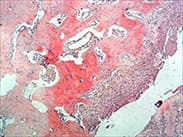

| 剛果紅染色 | 淀粉樣蛋白 | 確定組織中無形物質(zhì)的性質(zhì),用于區(qū)分玻璃樣變(慢性結(jié)膜炎、肺的淀粉樣瘤、甲狀腺骨髓樣癌,胰島細(xì)胞瘤等) | ![]() |